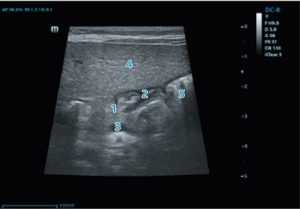

Рис. 2. Эхографическая визуализация пилорического отдела желудка: 1 — тело поджелудочной железы; 2 — пилорический канал; 3 — селезеночная вена; 4 — паренхима печени; 5 — желудок

Fig. 2. Echo-graphic visualization of the pyloric part of the stomach: 1 — body of the pancreas; 2 — pyloric canal; 3 — splenic vein; 4 — liver parenchyma; 5 — stomach